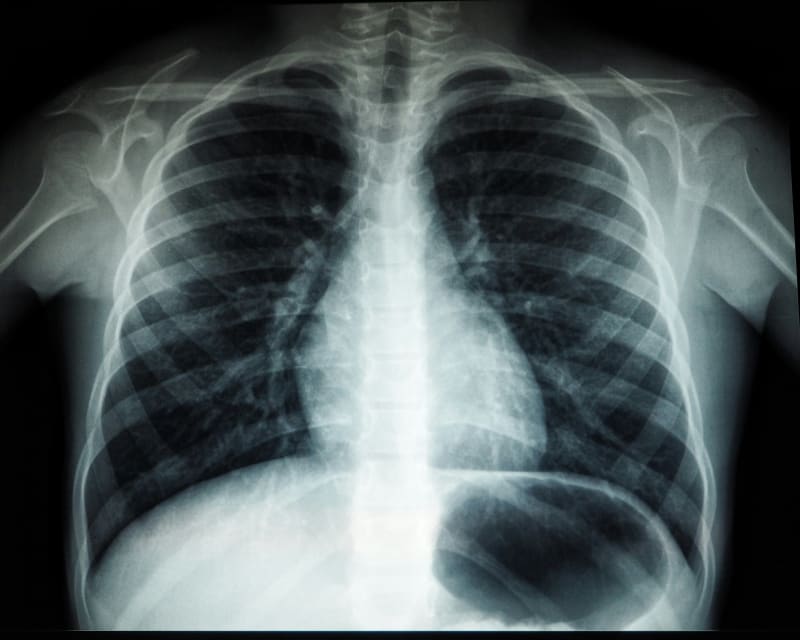

EU Women's Lung Cancer Deaths Finally Leveling Off in 2026

After 25 years of steady increases, lung cancer deaths among European women are predicted to stabilize in 2026, thanks to declining smoking rates. Millions of lives have been saved since 1988 through tobacco control policies across Europe.

For the first time in a generation, European women are seeing a turning point in the fight against lung cancer.

New research predicts that lung cancer death rates among women in EU countries will finally level off in 2026 after climbing steadily for more than 25 years. The stabilization comes as decades of tobacco control policies begin showing results, with death rates holding steady at around 12.5 deaths per 100,000 women.